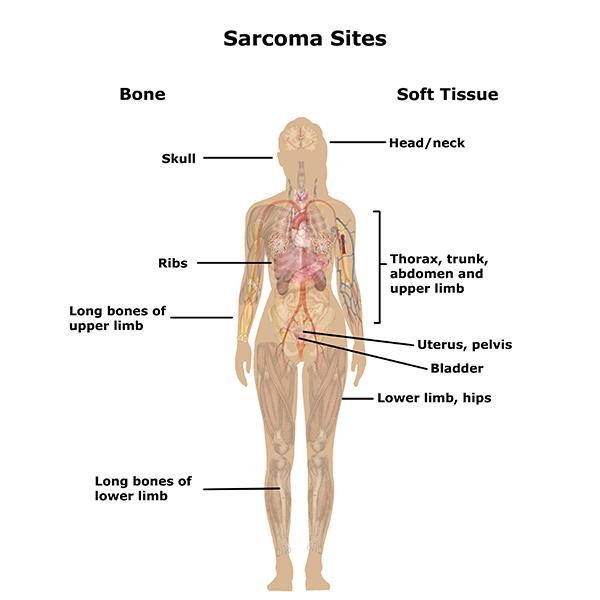

Soft Tissue Sarcoma

Soft tissue sarcoma is a infrequent type of cancer that start in the tissues that connect, support and surround other body structures. ...